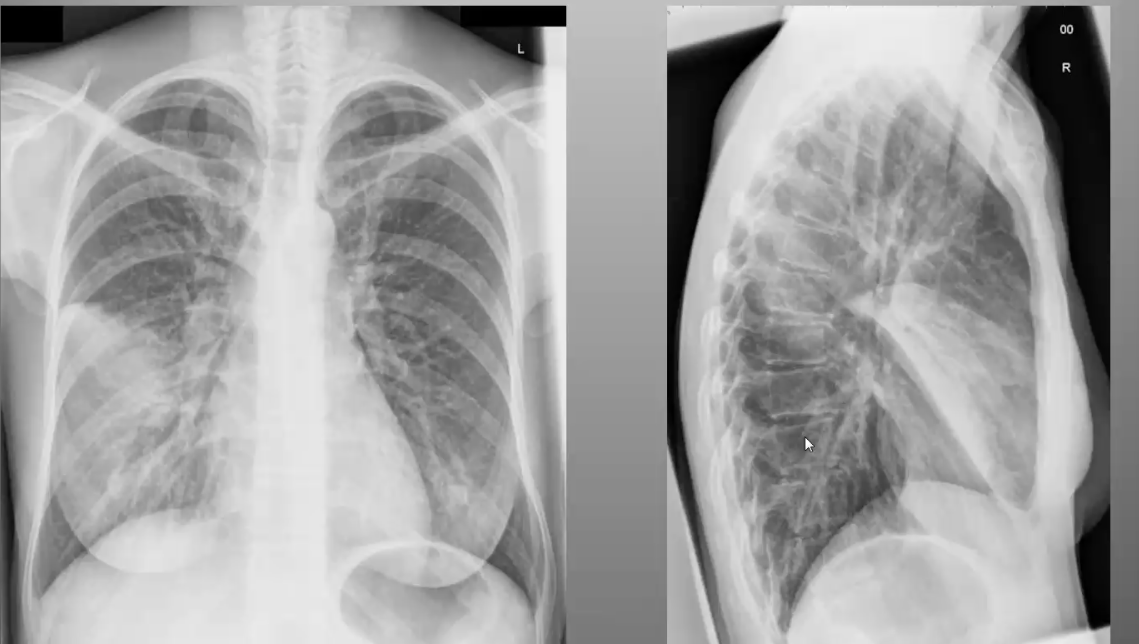

What’s your diagnosis?

Pulmonary edema